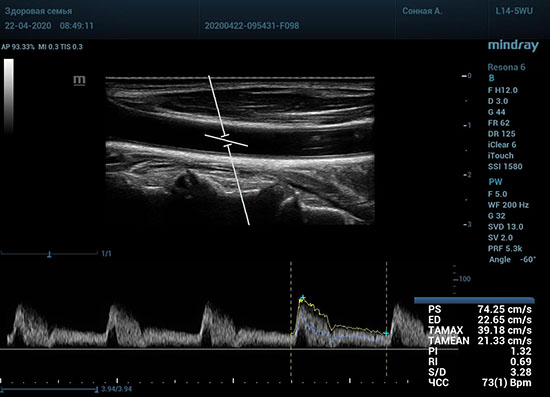

Особо ценна данная функция при исследовании тяжести стеноза. Доктор проводит санирование методом «утюжка» или же проводит «прогулку по стенозу» смещая зону опроса импульсно-волнового допплера. Таким образом проводит поиск максимальную скорость в струе элайзинга. Ранее максимальная скорость определялась на глазок, с дальнейшим измерением, либо серией измерений вручную. Теперь прибор сделает всё сам, без отрыва от движения, автоматически измеряя её в режиме реального времени.

Какие показатели выдает автоматический расчет? Доктор может настроить расчет под себя, под свои собственные желания. Стандартно выставлены показатели пиковой (PS) и конечной диастолической скорости (ED), TAMAX, TAMEAN, Pi, Ri, S/D соотношение и ЧСС. Можно дополнить из списка показателей: MD, PPG, Объемный поток, DT, AT, MPG, MMPG, VTI, D/S соотношение. Прибор подстраивается под Вас, а не вы под прибор.